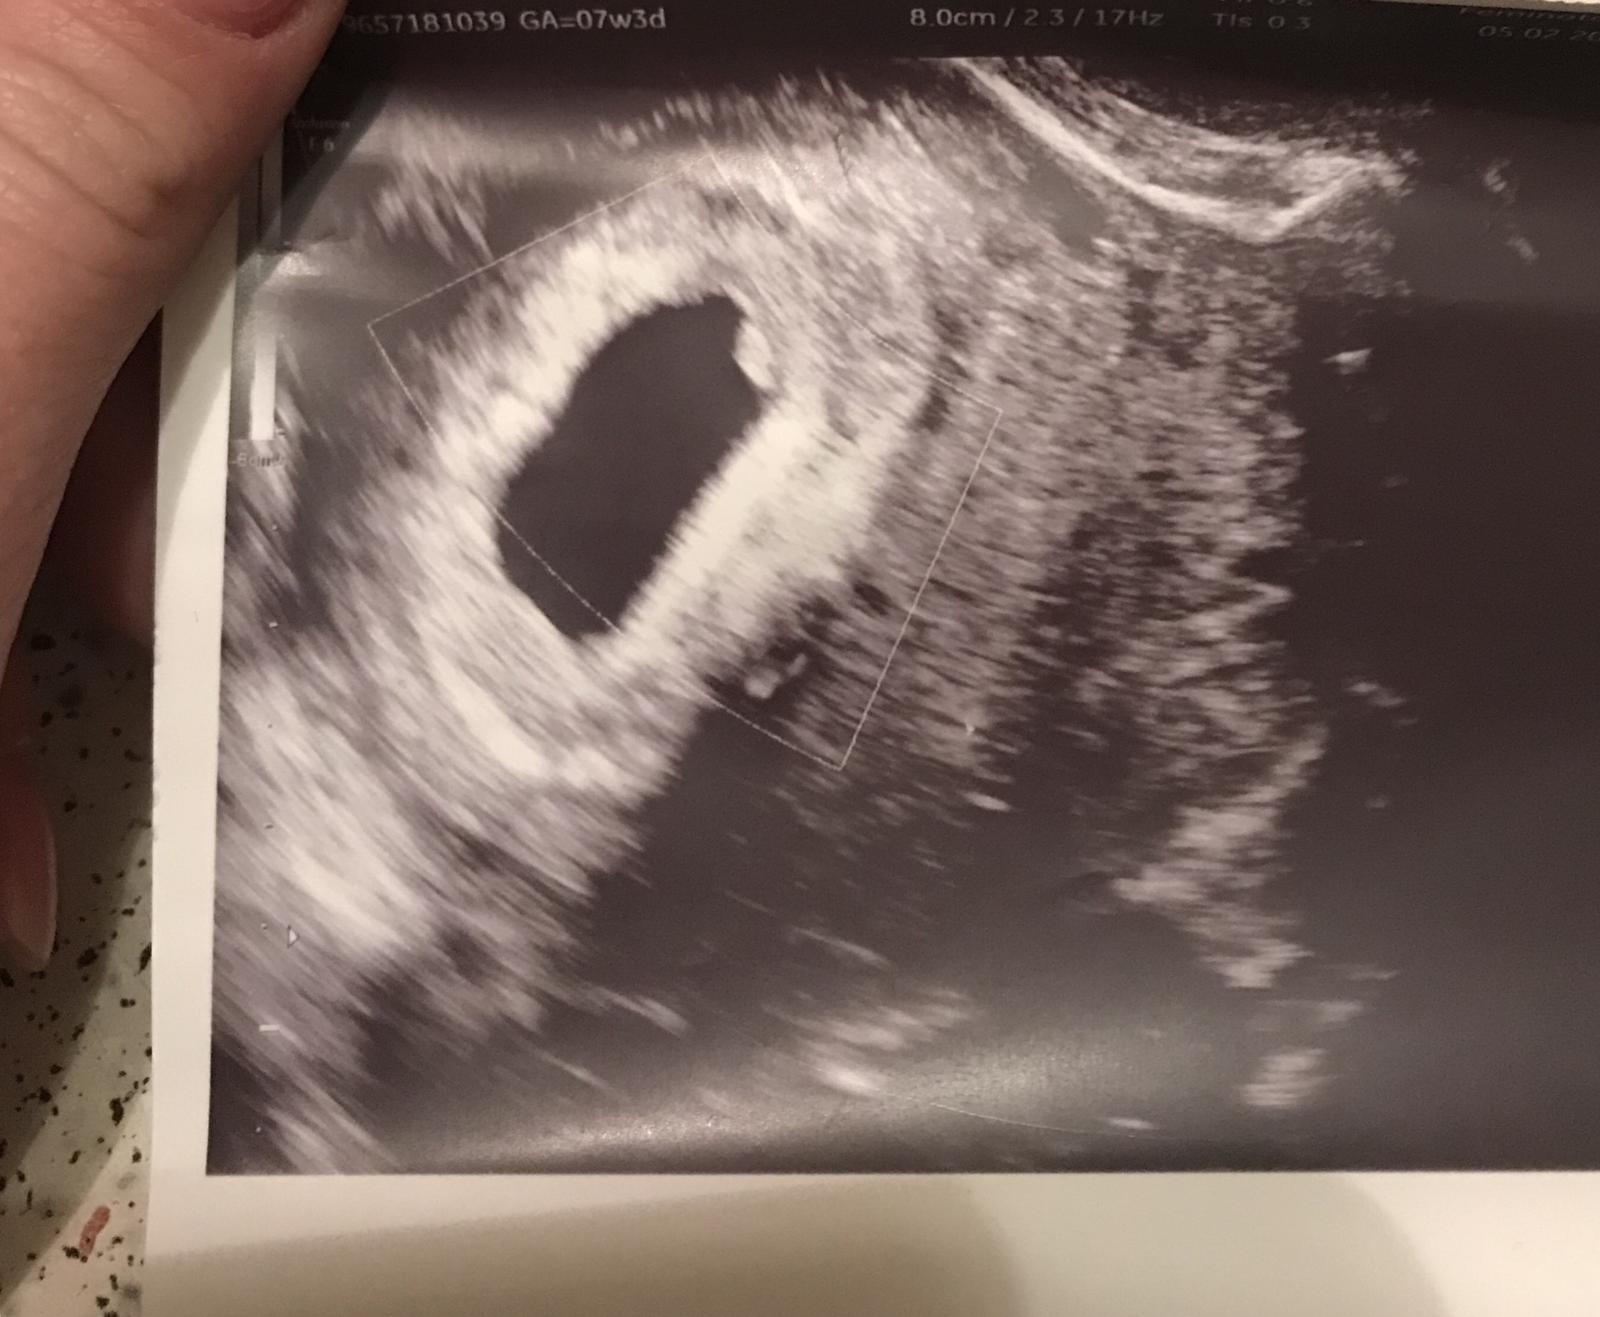

Tak tu je nás pokladik ❤️ Krásne sa vrtelo ☺️